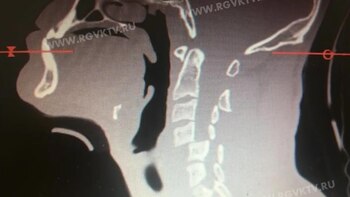

El resultado fue una fractura en las vértebras cervicales, una lesión en su médula espinal, un trauma craneoencefálico y una contusión cerebral.

Aliev Payzutdin permaneció totalmente inmóvil mientras que su rival y el árbitro fueron a ver qué estaba ocurriendo. Finalmente, el hombre fue trasladado al Janelidze Research Institute of Emergency Medicine, en donde se le realizaron distintas tomografías.